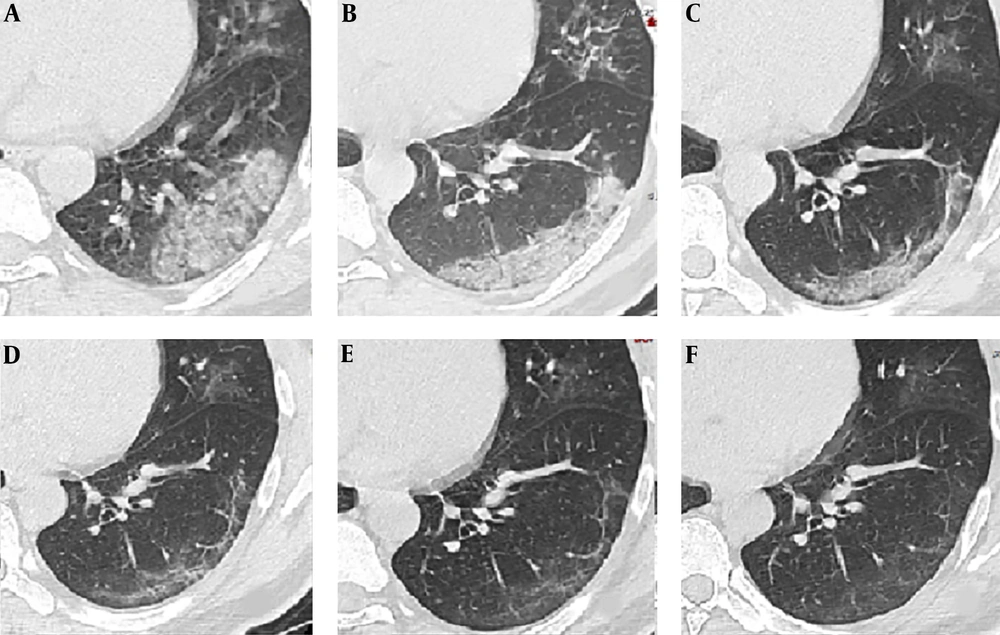

4.3. Follow up CT

CT image findings of a 41-year-old male on the 2nd (stage-1), 7th (stage-2), 12th, 16th, 21th, and 24th day (stage-3) demonstrated crazy paving GGO mixed with partial consolidation pattern (pattern E) (A), consolidation pattern (pattern F) (B, C), strip-like opacity pattern (pattern G) (D), minimal parenchymal bands pattern (pattern H) (E) and multiple GGO pattern (pattern B) (F) respectively.